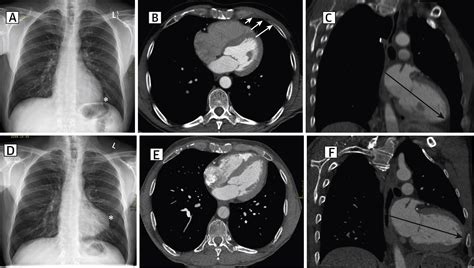

• xray boot shaped heart

• tetralogy of fallot

• boot shaped heart radiology

• boot shaped heart causes

• tetralogy of fallot radiopaedia